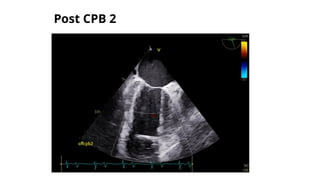

POST CPB 2

POST CPB TEE

oP/VSR+LV apical exclusion+CABG

oFair LVSF, EF=40%, CO=4.7 L/min, CI-2.4 L/min/m2

oContractility improved with inotropes

oMild MR/TR